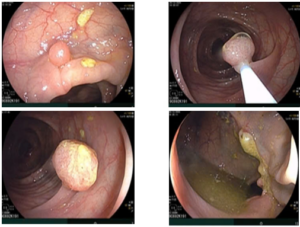

CASE LÂM SÀNG: CHẨN ĐOÁN BỆNH NHÂN ĐỒNG MẮC BA LOẠI UNG THƯ TẠI TRUNG TÂM Y HỌC HẠT NHÂN VÀ UNG BƯỚU, BỆNH VIỆN BẠCH MAI

CASE LÂM SÀNG: CHẨN ĐOÁN BỆNH NHÂN ĐỒNG MẮC BA LOẠI UNG THƯ TẠI TRUNG TÂM Y HỌC HẠT NHÂN VÀ UNG BƯỚU, BỆNH VIỆN BẠCH MAI GS. TS. Mai Trọng Khoa, PGS. TS. Phạm Cẩm Phương, PGS. TS. Phạm Văn Thái, BSNT. Đỗ Thị Thu Trang Trung tâm Y...